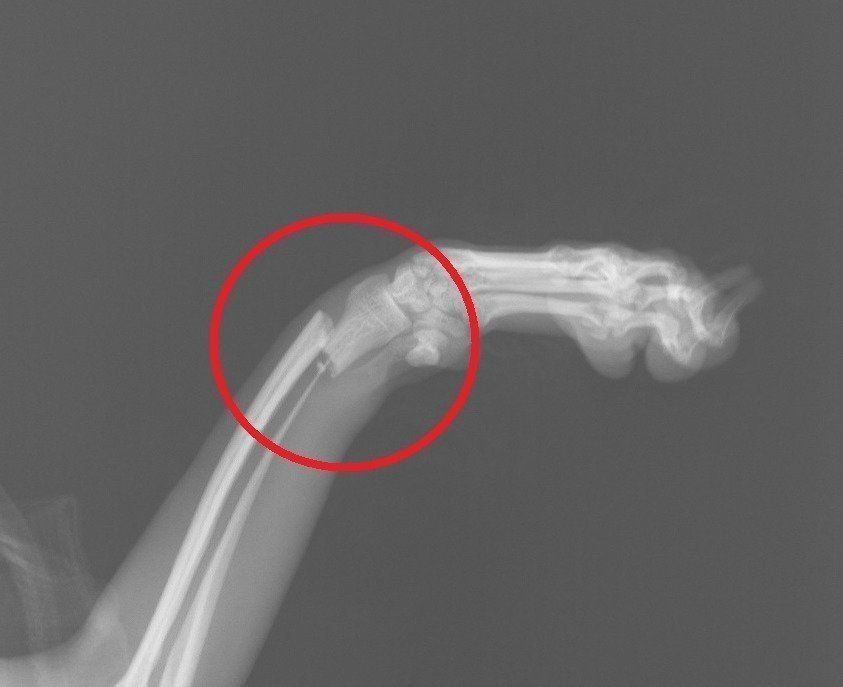

症例写真提供/ノヤ動物病院

画像は、前足を骨折した、7カ月のトイ・プードルのエックス線写真。赤い丸で囲まれた箇所が症状の見られる部分です。